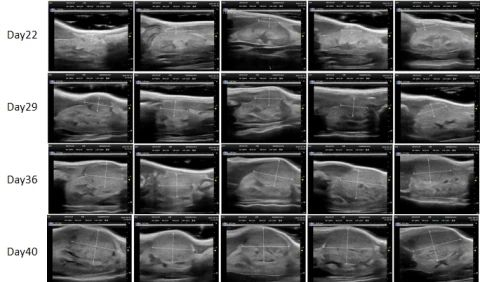

PDX Model (Growth Curve)

部分HJC黄金城平台PDX原位模型展示